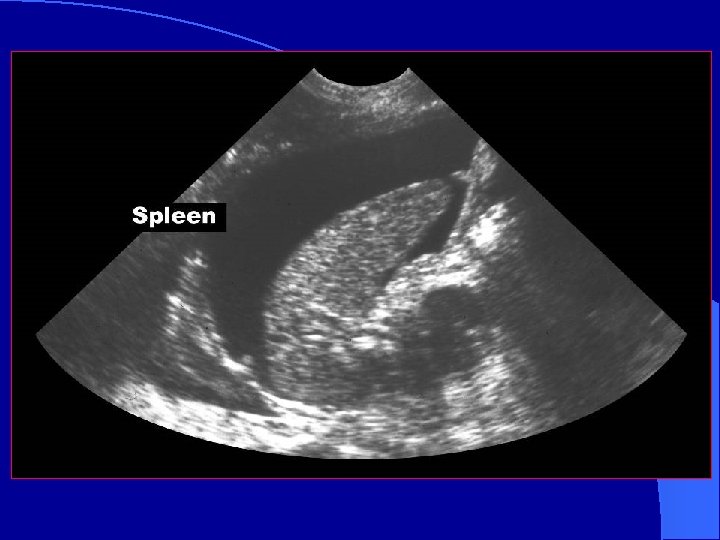

LUQ Scan Plane l More difficult – Acoustic window (spleen) is smaller than liver – Mild inspiration will optimize image – Bowel interference is common

LUQ Scan spleen * * * kidney * *Splenorenal fossa – a potential space

Normal Spleno -renal view Free fluid around spleen